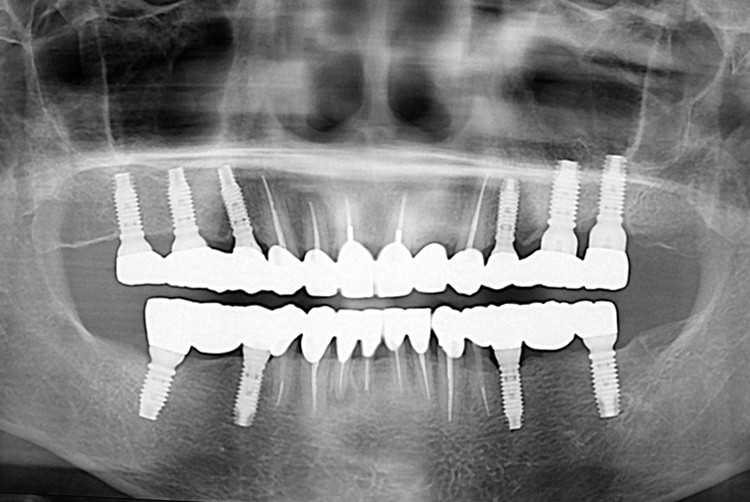

02f51832a1263f0919fc49bd2129faad.jpg

치료전 : 2019-10-08

1817 홍종름_후.jpg

치료후 : 2019-12-14

세종치과는 많은 환자와 다양한 케이스를 바탕으로 항상 편안한 임플란트 수술을 제공하고자 노력하고,

오래동안 튼튼히 쓸 수 있는 임플란트 수술을 가장 큰 목표로 삼고 있습니다